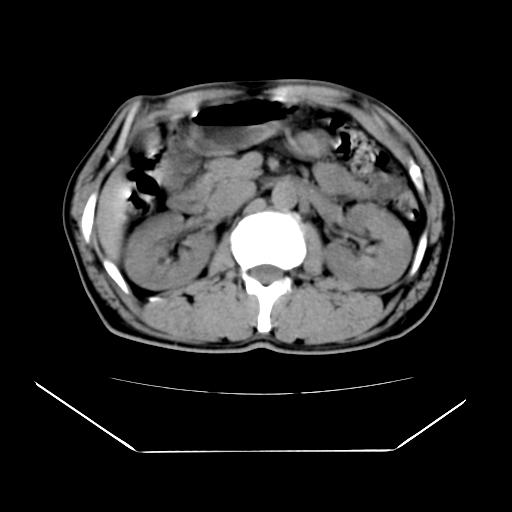

男性,55岁,外院体检afp明显升高,但b超未发现异常,否认乙肝病史。来我院ct增强。有延时扫描。

肝脏右叶动脉期可见低密度影,至延迟期被充填,考虑血管瘤可能性大。

肝右叶病灶

不排除肝右叶肝癌可能。

这个不是肝右静脉吗,这么大的病灶b超不可能发现不了吧

如果这个是癌灶的话则下腔静脉有瘤栓可能

肝6段血管瘤

血管瘤可能性大。

是肝右静脉吧

考虑肝右静脉影。